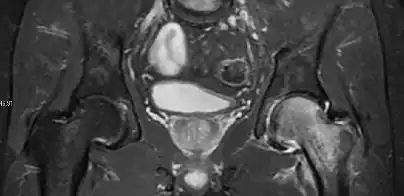

Figure 8:

-

X-ray of a patient with transient osteoporosis of the left hip showing osteoporosis.[1] -

Coronal stir imaging in transient osteoporosis, showing diffuse edema.[1] -

Scintigraphy (A), sagittal T1 (B), and coronal PD fat sat of a patient with a subchondral fracture of the femoral head with convex shape to the articular surface.[1] -

Coronal T1 of a patient with avascular necrosis of the femoral head.[1]